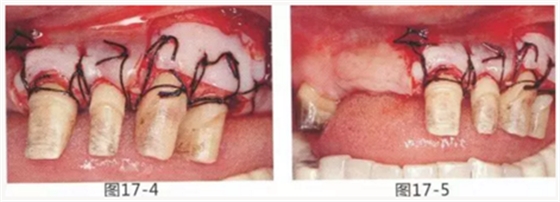

圖17-1~3 左上3的牙周袋探測值為3mm,角化牙齦寬度為2mm。也就是完全不存在附著齦,如果這種狀態(tài)下佩戴修復體的話,很有可能發(fā)生頸部暴露等問題。

圖17-4 左上1,2進行齦瓣根尖側轉移,左上3,4進行游離牙齦移植,在去除牙周袋的同時獲取附著齦。

圖17-5 牙周治療完成后的正面照。左上3,4部位處游離齦移植片的上端通過骨膜縫合固定在頰側嵴頂部。這樣可以使其愈合效果與齦瓣根尖側轉移相同。